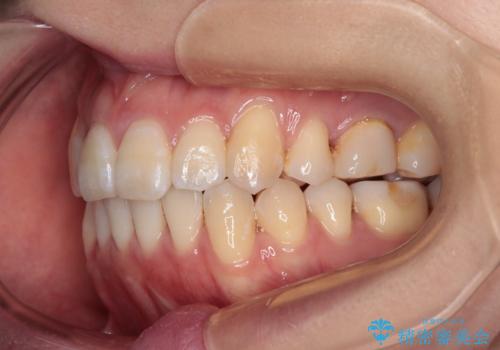

開咬の改善にはインビザラインが有効であり、インビザライン単体での治療を検討しましたが、上顎前突を回避するために上顎左側第一小臼歯抜歯を行うこととしたため、補助装置とワイヤー矯正を併用した上で、インビザラインによる矯正治療を行うこととしました。

インビザライン矯正治療では、臼歯の圧下による前歯部の早期接触が大きな問題となっています。開咬では、その臼歯圧下を逆手にとって前歯部の非接触を改善させることができます。